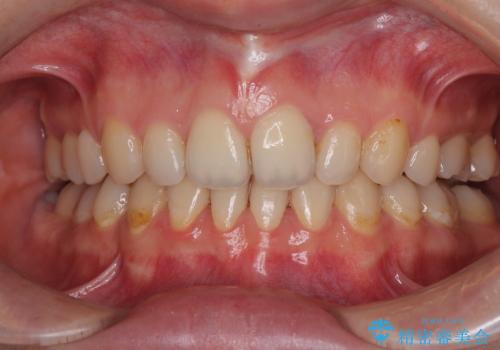

しみる前歯のセラミック治療 周辺も同時に治療して調和の取れた前歯に